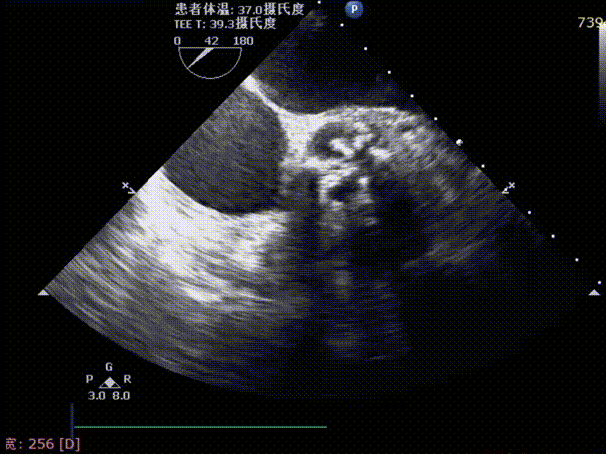

入院心超提示:Vmax 5.41m/s,PGmean 70mmHg,诊断为重度主动脉瓣狭窄伴少量反流,二尖瓣轻度狭窄伴少量反流,三尖瓣少中量反流。

术前TEE评估主动脉瓣

释放后超声下多切面评估,瓣膜位置可,无明显瓣周漏

测得主动脉瓣流速由5.4m/s改善至1.9m/s